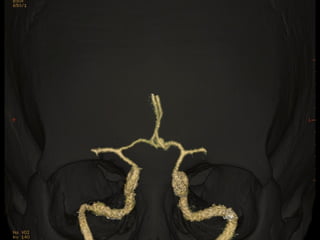

Hémorragie sous-arachnoïdienne (HSA)

Rupture d’anévrysme

ArtériographieAngioscanner